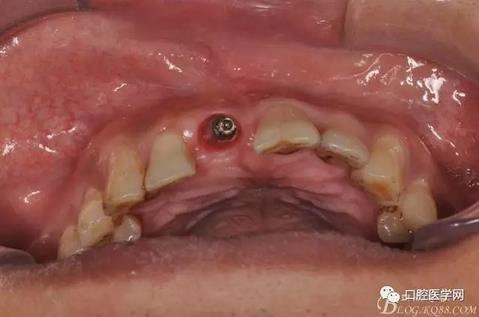

圖7 術(shù)后植入愈合基

圖8 術(shù)后即刻臨時(shí)冠修復(fù)